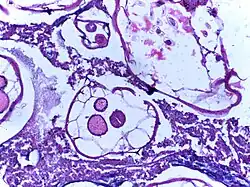

_(15806559913).jpg)